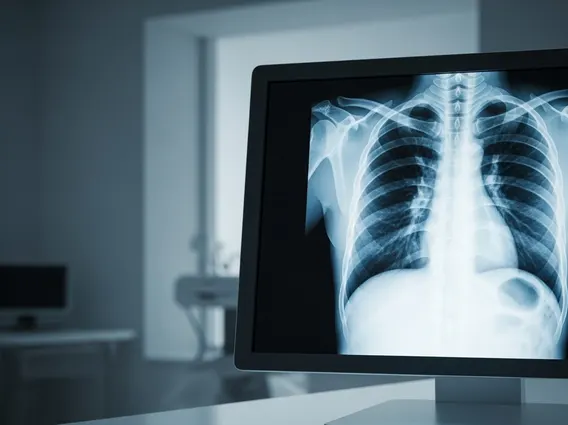

What is Thoracic: Anatomy and Function

The term Thoracic refers to the chest area of the body, situated between the neck and the abdomen. This critical region is defined by the rib cage, sternum (breastbone), and the vertebral column, specifically the thoracic spine explained as the middle section of the spine, comprising twelve vertebrae (T1-T12). These vertebrae are unique because they articulate with the ribs, forming a protective cage around vital organs. The primary function of the thoracic region anatomy and function centers on protecting the heart and lungs, facilitating respiration, and providing structural support for the upper body.

What is the Thoracic Cavity

The thoracic cavity is the space enclosed by the ribs, vertebral column, and sternum, and is separated from the abdominal cavity by the diaphragm. This vital cavity is subdivided into three main compartments: the two pleural cavities, each housing a lung, and the mediastinum, located between the lungs. The mediastinum contains the heart, major blood vessels (aorta, vena cava), trachea, esophagus, and thymus gland. The robust bony framework of the thoracic cavity provides essential protection for these delicate and life-sustaining organs from external trauma.